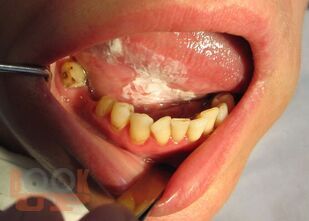

Злокачественные новообразования и восстановительная хирургия челюстно-лицевой области

Учебное пособие предназначено для студентов стоматологических факультетов, врачей-интернов, врачей-ординаторов, стоматологов, челюстно-лицевых хирургов практического здравоохранения.

Приведены материалы по общим и частным вопросам онкостоматологии и восстановительной хирургии челюстно-лицевой области. Изложены принципы обследования и современные методы лечения больных с онкопатологией челюстно-лицевой области, в соответствии с общепринятой классификацией описывается клиника отдельных нозологических форм заболеваний.

Описаны показания и противопоказания к восстановительным и реконструктивным операциям челюстно-лицевой области, принципы их планирования.